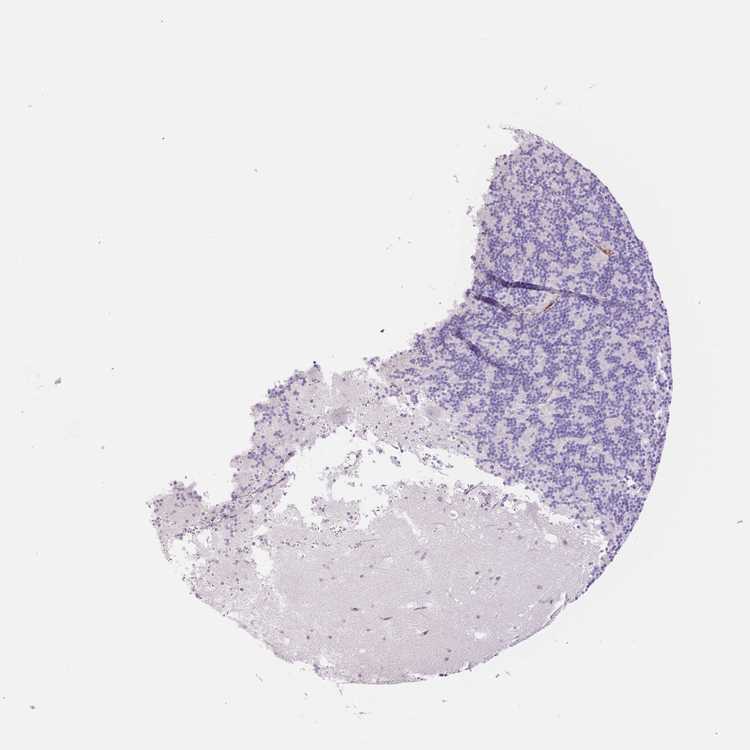

CEREBELLUM - Antibody stainingi

Antibody staining in the annotated cell types in the current human tissue is reported as not detected, low, medium, or high, based on conventional immunohistochemistry profiling in selected tissues. This score is based on the combination of the staining intensity and fraction of stained cells.

Each image is clickable and will lead to virtual microscopy that enables deeper exploration of all samples and also displays staining intensity scores, fraction scores and subcellular localization as well as patient and tissue information for each sample.

Antibody HPA004114Antibody HPA045134Antibody CAB068203

Purkinje cells Not detectedNot detectedNot detected

Cells in granular layer Not detectedNot detectedNot detected

Cells in molecular layer Not detectedNot detectedNot detected